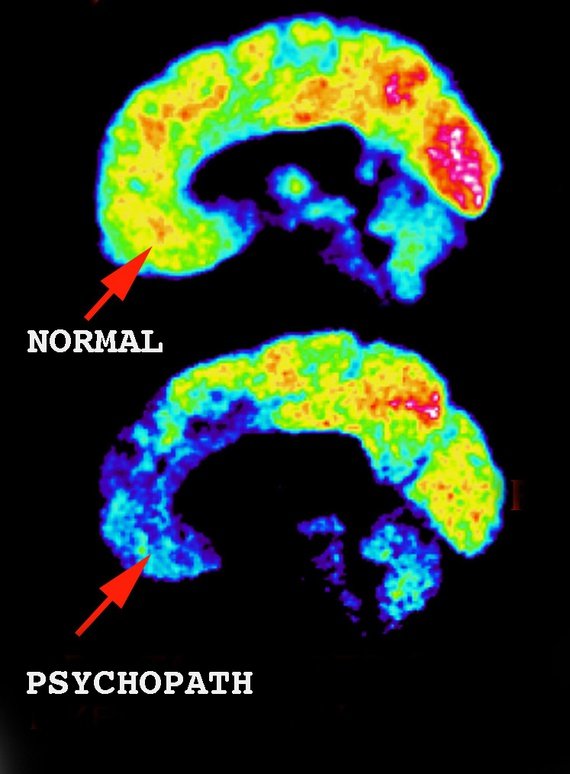

사이코패스와 일반인의 뇌 비교

뇌의 앞부분(전전두피질, 의사결정, 사회적 행동, 성격 표현)과 가운데 작은 영역(감정을 담당하는 편도체)은 사이코패스의 뇌에서 불이 들어오지 않는 것이 보인다. 이러한 영역에서 활동이 거의 또는 전혀 없음을 의미한다.

사이코패스의 뇌는 사이코패스가 사회의 작은 부분을 대표하면서도 심각한 범죄 행위를 저지른다는 사실 때문에 수십 년 동안 연구의 관심 대상이었다. 자기 공명영상(MRI) 스캔 또는 기능적 MRI(fMRI) 스캔을 받는 사이코패스가 점점 더 많아짐에 따라 몇 가지 상관관계가 발견되었다. 확실히 사이코패스의 뇌는 일반 뇌와 다르다.

사이코패스의 뇌 스캔 결과에서 큰 차이를 보이는 세 가지 주요 부분이 있다. 편도체, 전두엽 피질 및 확장된 변연계 구조의 영역이다. 이 영역에 미치는 영향은 정신병적 증상을 유발하는 것일 수 있으며 정신병적 성격이라고 진단 내릴 수 있는 기준이 된다.